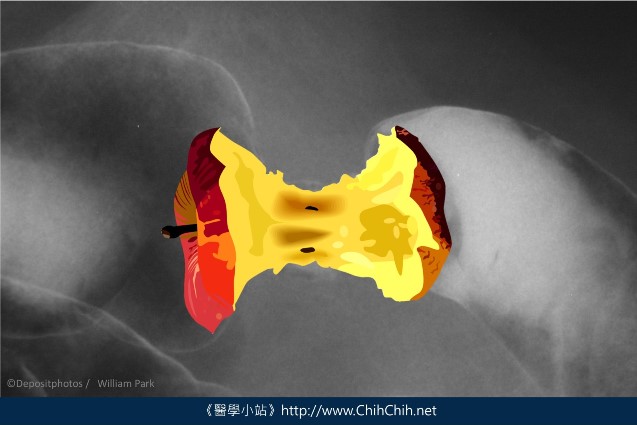

這張圖是由下消化道攝影所發現的大腸癌,原本寬闊、平順的腸道變得狹窄又凹凸不平,看起來就像吃剩的蘋果核。

這種大腸癌便會在影像上出現典型的蘋果核,厚實的腫瘤沿著腸道長成一整圈,使管徑變小,固態糞便就不容易通過。患者的排便習慣可能變得很紊亂,時而便秘,時而拉稀。